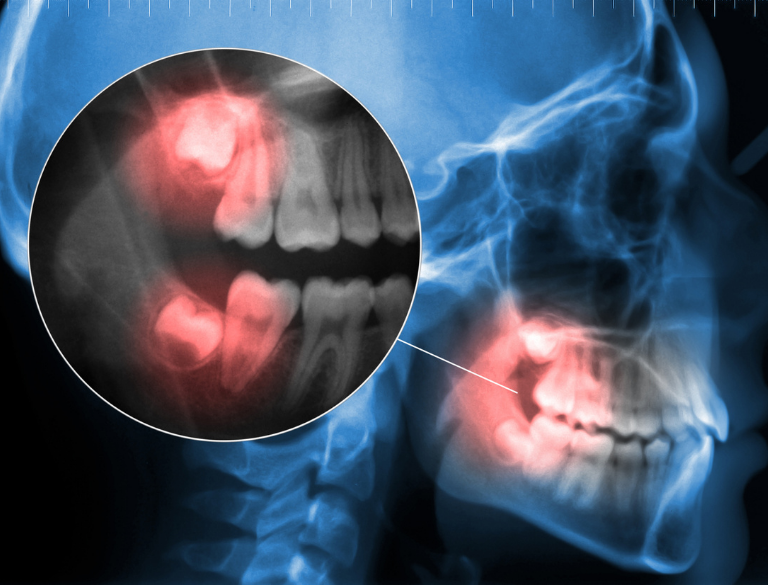

Wisdom Tooth Extractions

Wisdom teeth can cause significant pain, swelling, and infection when they become impacted. Our team specializes in safe and efficient wisdom tooth removal to prevent complications.

- Minimally invasive techniques to reduce discomfort.

- Sedation dentistry available for anxiety-free extractions.

- Quick recovery with advanced post-operative care instructions.